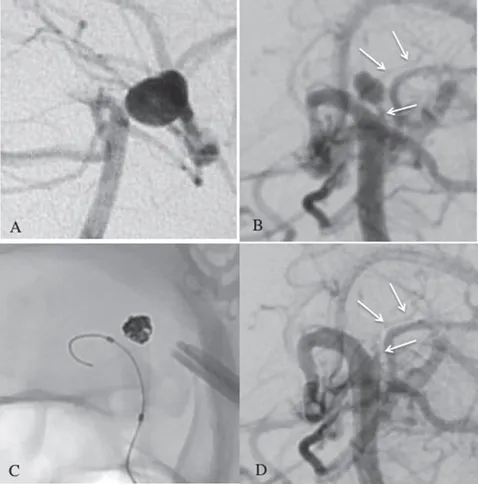

A. 显示七年前术后动脉瘤夹闭状态;B. 此次发病,新动脉瘤在旧动脉瘤夹旁显现;C与D. CT图像显示广泛的蛛网膜下腔出血。

面对已陷入昏迷的符女士,治疗团队必须立即采取行动。首要任务是处理急性脑积水(由出血阻塞脑脊液循环通路引起),团队为其进行了双侧脑室外引流术,以稳定基本生命体征。随后,通过清晰度更高的数字减影血管造影(DSA)检查,动脉瘤的细微结构得以清晰显现。

此次高难度的“拆弹”任务由主刀的川岛明次教授团队承担。术后造影证实,动脉瘤已完全不再显影,同时所有重要的穿支血管均得到了完好保留。